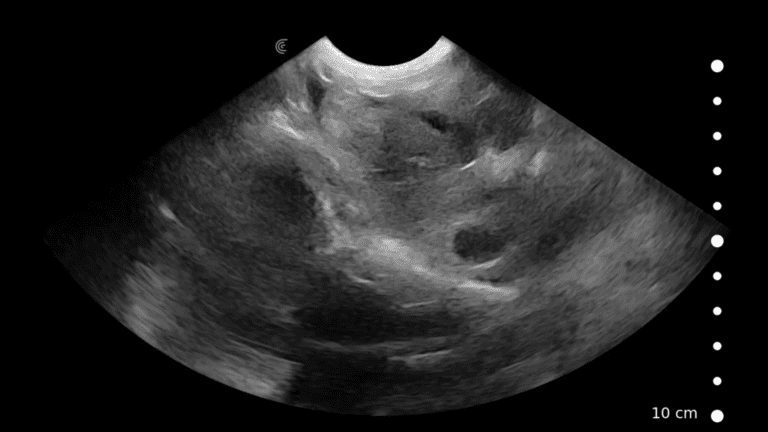

Canine: Adrenal Glands

In this video Dr. Camilla Edwards shares her technique for imaging the adrenal glands in a dog. She provides useful landmarks to identify their location, and describe the ultrasound appearance of normal adrenals.